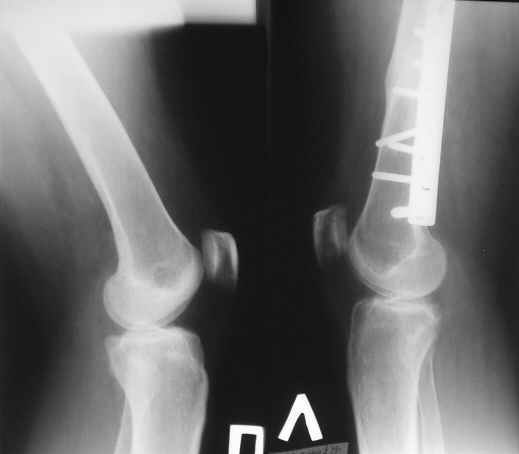

На консультацию пришла женщина, 40 лет. В 2004г. автодорожная травма - перелом бедра. Остеосинтез пластиной. Мягкие ткани зажили первичным натяжением, перелом сросся.

Укорочение бедра 0,5 см. Беспокоят постоянные боли в области колена. Снимки на руках были только вот эти.

Думаю, что оперировавшие коллеги не устранили ротационное смещение. Какие у кого соображения в отношении дальнейшей тактики?

Посмотрев рентген возник вопрос. В пластине ли дело? В нижней трети бедреннй кости и дистальном эпифизе участок порозности с довольно четкими контурами. Возможно формируется или сформировалась киста. Иногда они дают боли за счет повышения внутрикостного давления.